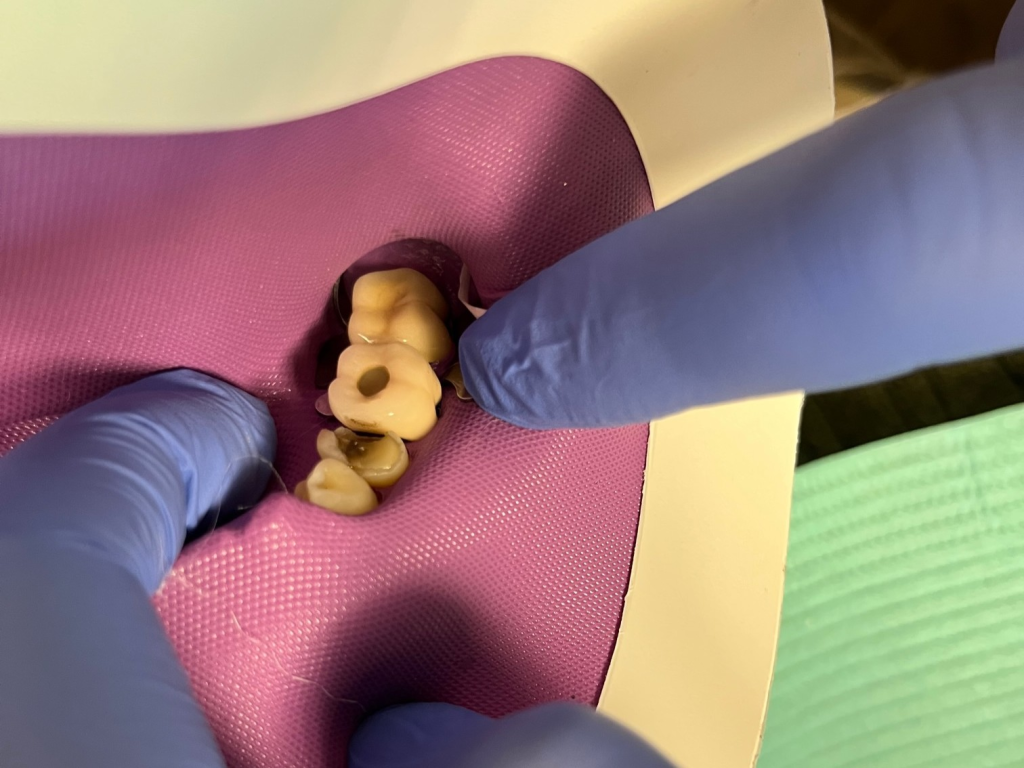

Posterior DentXpinTM repair.

5